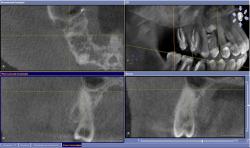

• Вопрос о необходимости эндодонтической терапии при наличии обширного кариозного поражения можно решить, проведя качественное диагностическое исследование с помощью челюстно-лицевого компьютерного томографа (рис. 47-50):

| Рис. 47 Фрагмент ортопантомограммы и фронтальный срез по оси, проведенной от вершины небного бугра к верхушке корня 1.5 зуба |

| Рис. 48-50 Профильные срезы через коронковую часть пульпарной камеры 1.5 зуба – небно: дистальная полость; фронтальный срез – вестибулярно: полость на медиальной поверхности |

• На основании 3D исследования, выявившего апроксимальные кариозные полости, затрагивающие пульпарную камеру, и на дистальной и на медиальной поверхностях 1.5 зуба, планируется эндодонтическое лечение.